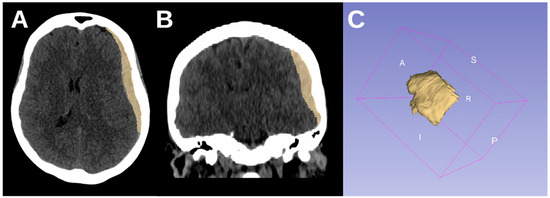

To illustrate this, Figure 3 and Figure 4 provide representative CT images of aSDH cases from our cohort with generalized seizures but different elongation values. Figure 3 shows a case with high elongation (1.99615), where the hematoma presents a markedly stretched, crescentic morphology with extensive cortical contact, aligning with our findings that higher elongation is associated with increased seizure risk. In contrast, Figure 4 depicts a case with lower elongation (1.38206).

Figure 3. CT axial (A), coronal (B), and 3D reconstruction (C) of an acute subdural hematoma with high elongation (1.99615) in an 88-year-old male patient with generalized seizures.